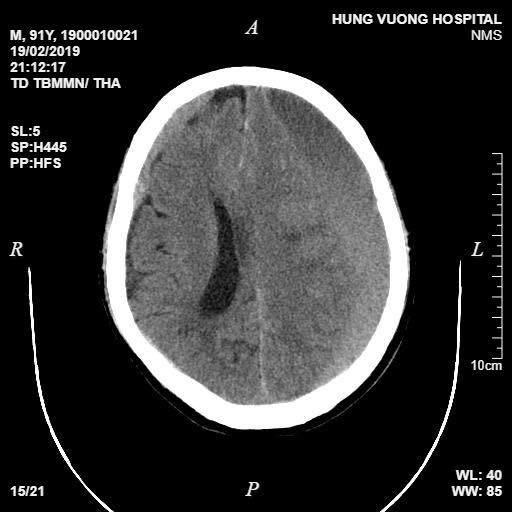

Kết quả cho thấy hình ảnh tụ máu dưới màng cứng bán cấp rộng hai bán cầu. Các tổn thương chèn ép nhu mô não và não thất đẩy lệch đường giữa sang phải 11mm; vỡ xương đỉnh phải.

Kết quả chụp CT cho thấy máu tụ dưới màng cứng của bệnh nhân. (Ảnh do bệnh viện cung cấp)